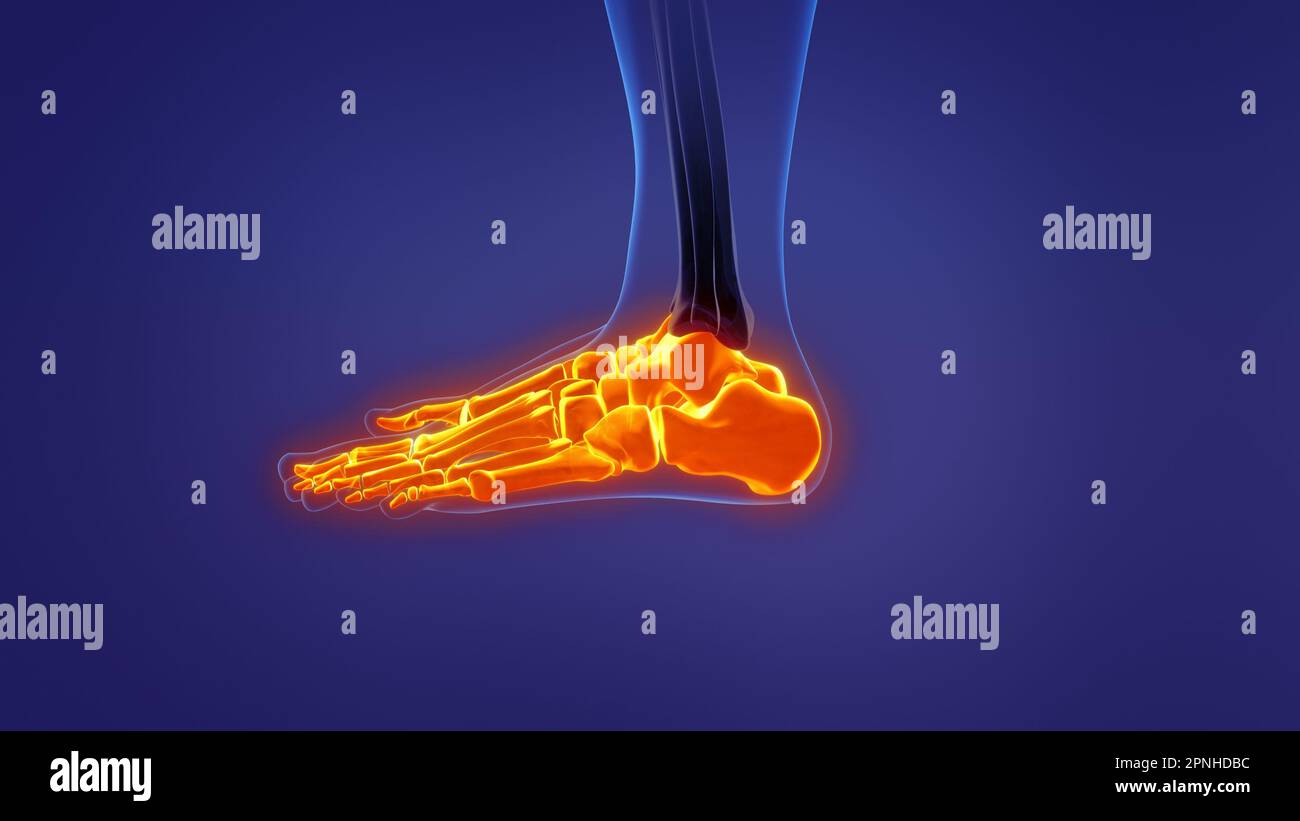

RF2R3WKY1–Illustration médicale des principales parties des os du pied en vue latérale, avec annotations.